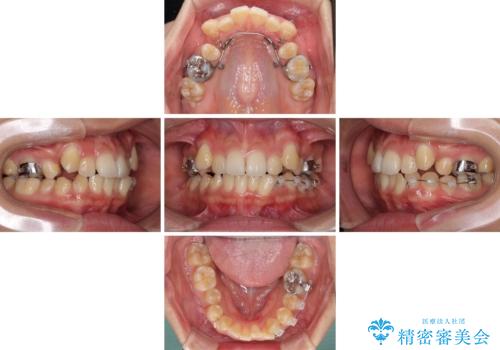

八重歯の移動量が多く、インビザライン単体での治療は困難と判断し、補助装置により八重歯移動後にインビザラインを用いることとしました。

装着時間をしっかりと守ってくださったので、予定通りの期間で終了することができました。